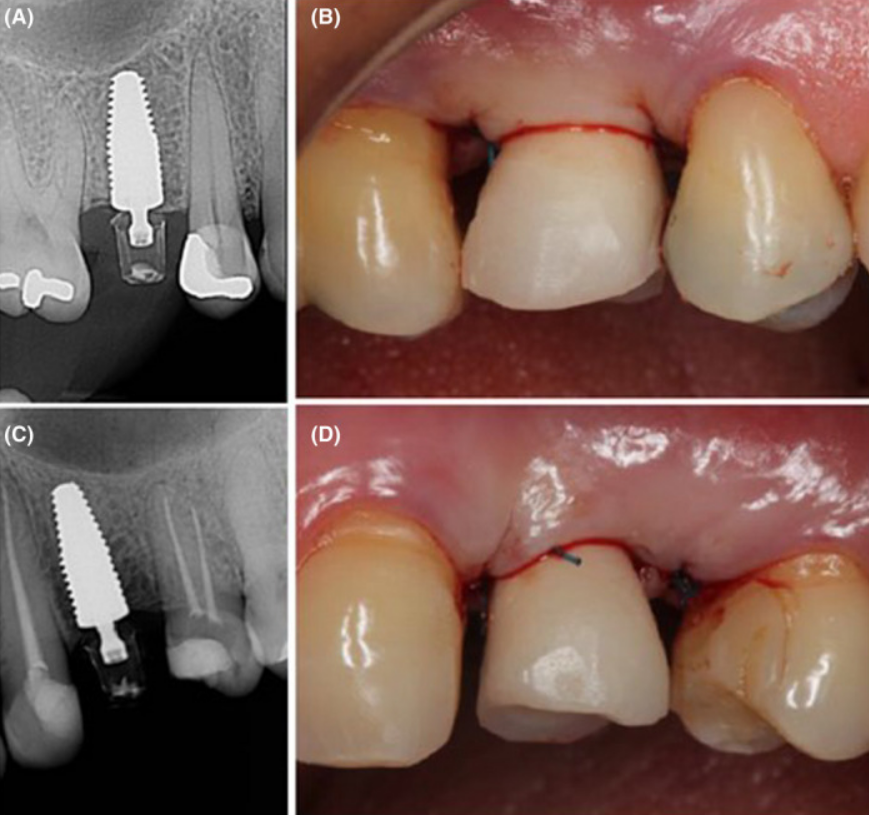

Клінічний випадок: заміщення втрачених 15 і 24 зубів за допомогою імплантатів Neodent Zirconia з подальшим протезуванням.

Фіксація постійних конструкцій через 3 місяці після хірургічного етапу.

Клінічна ситуація на огляді через 12 місяців.